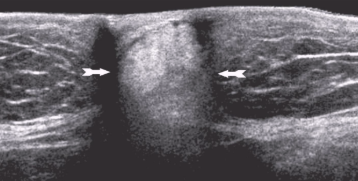

Hematoma

Collection of blood in tissue

Indication: trauma, pain, palp mass, ecchymosis, decreasing hematocrit

Can be uni or bilateral

US appearance:

Heterogeneous

Hypoechoic to hyperechoic

Fluid-fluid levels

Fluid can contain echogenic debris